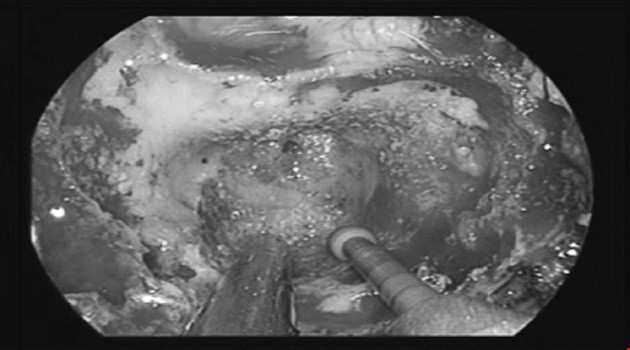

Các thiết bị kỹ thuật hỗ trợ cũng hết sức hiện đại với dao mổ siêu âm, hệ thống nội soi có định vị 3 chiều không gian, bác sĩ có thể nhìn rõ từng chi tiết nhỏ nhất bởi vì khi mổ mở dù có "tinh mắt" thế nào thì việc định vị khối u và "vùng nguy hiểm" cũng rất khó khăn.

Nhiều năm cầm dao mổ vùng đầu cổ nhưng bác sĩ Kỳ vẫn "toát mồ hôi" với ca mổ này, bởi chỉ sơ xuất chút nếu động vào động mạch cảnh, máu sẽ phun không cầm được như thế bệnh nhân sẽ tử vong.

Giải quyết xong khu vực của động mạch cảnh, đến phần thân sọ não cũng "toát mồ hôi hột". Tuy nhiên, may mắn khi bác sĩ thực hiện lấy u trên phần não thì khối u mới chỉ "ăn" đến phần màng cứng của não, chưa vào thân não nếu vào tới thân não thì còn phức tạp hơn rất nhiều.

Cuối cùng, là lấy u vùng tuỷ sống cổ. U đã ăn sang cả đốt sống C 1 nên bác sĩ Kỳ cho biết phải lấy u cẩn thận bởi nguy cơ liệt tứ chi của bệnh nhân rất cao nếu chạm vào tuỷ sống cổ của bệnh nhân.